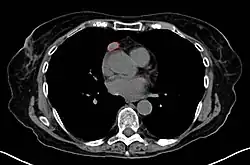

CT scan of the chest revealing a large necrotic mass in the left anterior mediastinum (indicated by the red line). Histology later established the diagnosis of a thymoma.

Another axial slice of a CT scan of the chest showing a small thymoma anterior to the heart (marked with the red line).

When a thymoma is suspected, a CT/CAT scan is generally performed to estimate the size and extent of the tumor, and the lesion is sampled with a CT-guided needle biopsy. Increased vascular enhancement on CT scans can be indicative of malignancy, as can be pleural deposits.[2] Limited biopsies are associated with a very small risk of pneumomediastinum or mediastinitis and an even-lower risk of damaging the heart or large blood vessels. Sometimes thymoma metastasize for instance to the abdomen.[6]